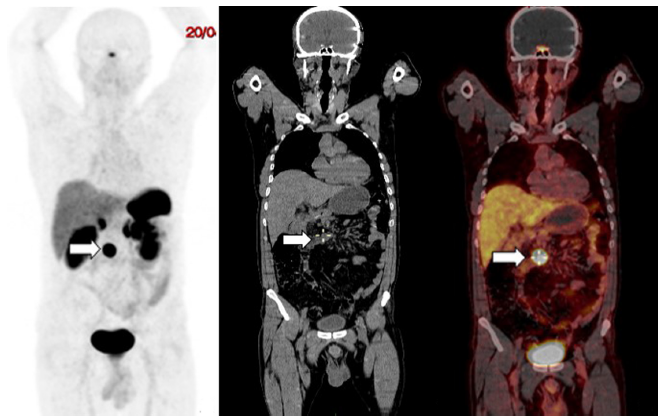

En septiembre de 2017 presentó deposiciones melénicas, por lo que se realizó una nueva EVDA en la que se encontró mucosa fundocorporal con eritema en parches, remanente del antro gástrico y luz intestinal normal. En octubre de 2017 se realizó una gammagrafía de receptores de somatostatina extrainstitucional, la cual presentó una captación en el mesogastrio paramedial derecho, Krenning 3/4, positivo para sobreexpresión de receptores de somatostatina, sugestiva de recurrencia tumoral. Por consiguiente, se realizó un PET/CT 68Ga-DOTANOC (3,5 mCi) (Figura 2) en abril de 2018 y se encontró un ganglio con sobreexpresión de receptores de somatostatina localizado en el mesenterio, por encima de la tercera porción del duodeno con medidas de 20 x 22 x 18 mm y valor máximo estandarizado de captación (SUVmáx) de 57,6 (Krenning 4/4), compatible con persistencia tumoral. No se observaron otras lesiones con sobreexpresión de receptores de somatostatina en el lecho quirúrgico o a distancia.

Figura 2 Paciente de 59 años, con TNE de duodeno. La PET/CT con 68Ga-DOTANOC mostró un ganglio con sobreexpresión de receptores de somatostatina, localizado en el mesenterio (flechas), por encima de la tercera porción del duodeno de 20 x 22 x 18 mm y SUVmáx de 57,6 (Krenning 4/4). A. Imagen de máxima intensidad. B. Corte coronal de TAC de baja dosis. C. Imagen de fusión de PET/CT.